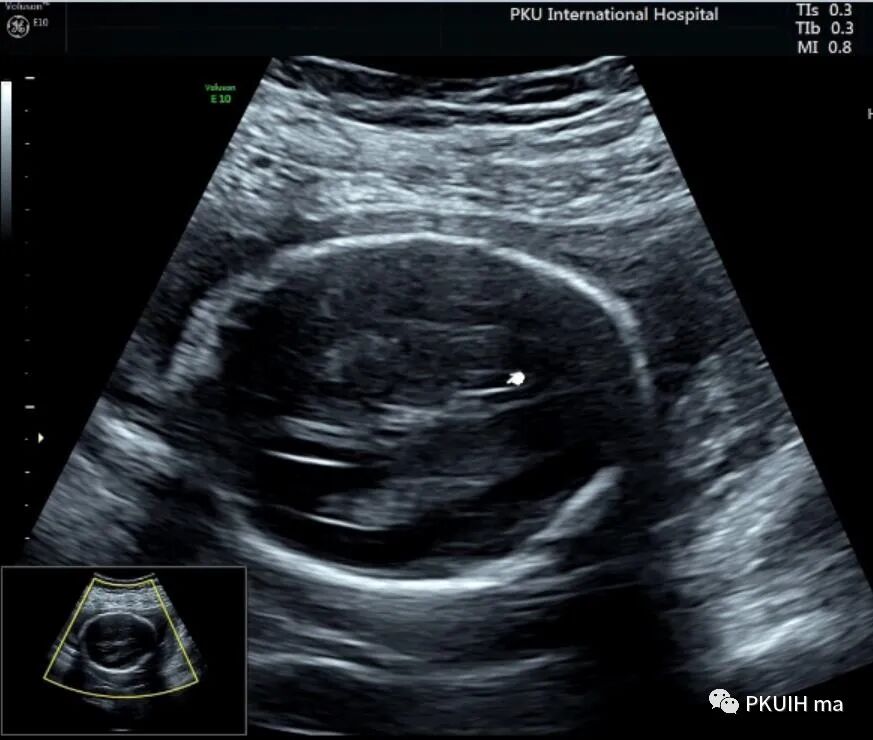

由于胎儿体位不好想着做一个三维,结果图像也不满意,只能等待胎儿仰卧或者俯卧观察正中矢状面了。

等了很久终于能打到一个矢状面的图像了,感觉胼胝体存在,长度还行,胼周动脉也有。由于孕妇太胖了怎么也打不好完整的胼胝体决定改天再观察。